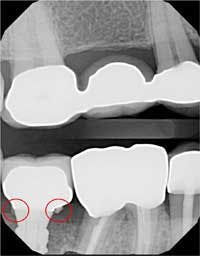

The screw channel of the abutment was accessed by carefully drilling a hole in the center of the occlusal surface using a cross-cut 557 bur (Brasseler) and progressively widening it until the screw channel was accessed (figure 10). Once the screw channel was accessed, the cavit and cotton blocking the screw were removed and the screw was visualized. A driver was placed into the channel to engage the screw and the cement-retained crown was seated on the implant and “screwed” back in place. Complete seating of the restoration was verified radiographically (figure 11). The screw was torqued to 25 Ncm and the access channel was filled with Teflon tape and closed with composite (figure 12). The patient was able to leave with the crown securely in place.

Figure 11:Complete seating of the restoration confirmed radiographically.